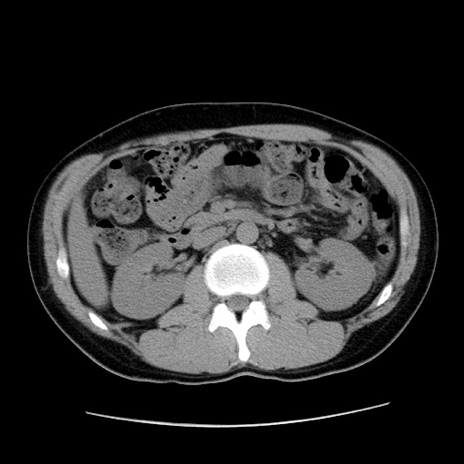

症例36(横断像)

【症例】20歳代 男性

【主訴】心窩部痛

【現病歴】今朝より上腹部痛あり。一旦軽快していたが再度出現したため救急要請。昨日夕に白身の魚を含む刺身を食べた。

【身体所見】BP 136/89mmHg、HR 74/min、BT 37.0℃、腹部:膨満、軟、心窩部に圧痛あり。反跳痛なし、筋性防御なし、腸雑音やや亢進あり。

【データ】WBC 17700、CRP 0.48